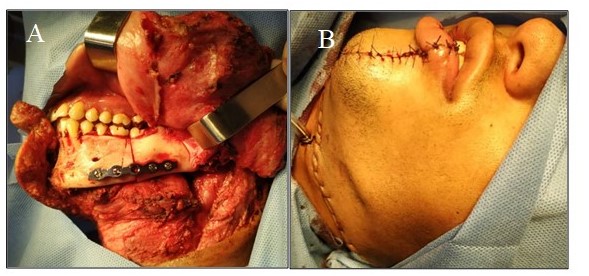

En vista de hallazgos, se discute en reunión de servicio multidisciplinaria y se decide llevar a mesa operatoria, realizándose resección oncológica de tumor en orofaringe a través de abordaje por swing mandibular por mandibulotomía lateral (Figura 6), más resección de fascia prevertebral y músculos pre vertebrales adyacentes más drilaje de cortical anterior de C1, C2 y C3, más colocación de material de osteosíntesis mandibular con placa de titanio 2,0 (Figura 7), traqueostomía y gastrostomía. Paciente permanece en unidad de terapia intensiva para cuidados posoperatorios, seguidamente en área de hospitalización, egresando sin eventualidades.

En resultado de biopsia definitiva, se concluye como sarcoma sinovial fusocelular (monofásico) de orofaringe (Figura 8), de 4,5 cm x 3,9 cm x 1,5 cm, grado 2 de FNCLCC, sin invasión linfovascular, márgenes quirúrgicos y ampliación libres de neoplasia. Se realiza estudio inmunohistoquímico (Cuadro 3), que indica sarcoma sinovial fusocelular (monofásico).

El Swing mandibular, corresponde a un abordaje quirúrgico cervical que está indicado en tumores grandes de la orofaringe, permitiendo obtener un gran campo quirúrgico (11). Se puede hacer mediante mandibulotomía lateral, mediana y para mediana. En el paciente que se presentó se utilizó este abordaje, mediante mandibulotomía lateral, lo cual facilitó la accesibilidad a la lesión y el campo operatorio, sin eventualidades.